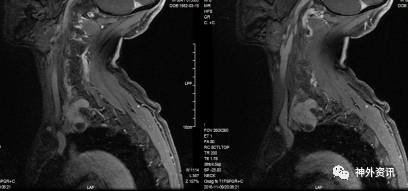

术后查体:左手五指背伸轻度受限,肘腕关节活动自如,左臂深浅感觉未见明显异常。复查颈部增强MRI示肿瘤全切(图7)。1月后随访,左手五指背伸功能恢复,无明显神经功能障碍。

图7. 术后MRI检查可见左颈部术后改变,肿瘤全切,瘤腔少量积液积气。胸膜腔未见破损。